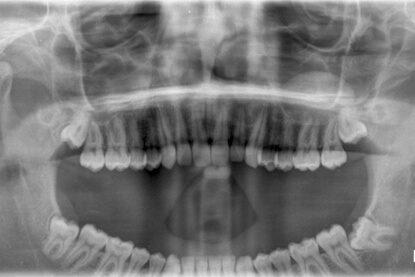

أنواع الأشعة السينية للأسنان:

بانورامي